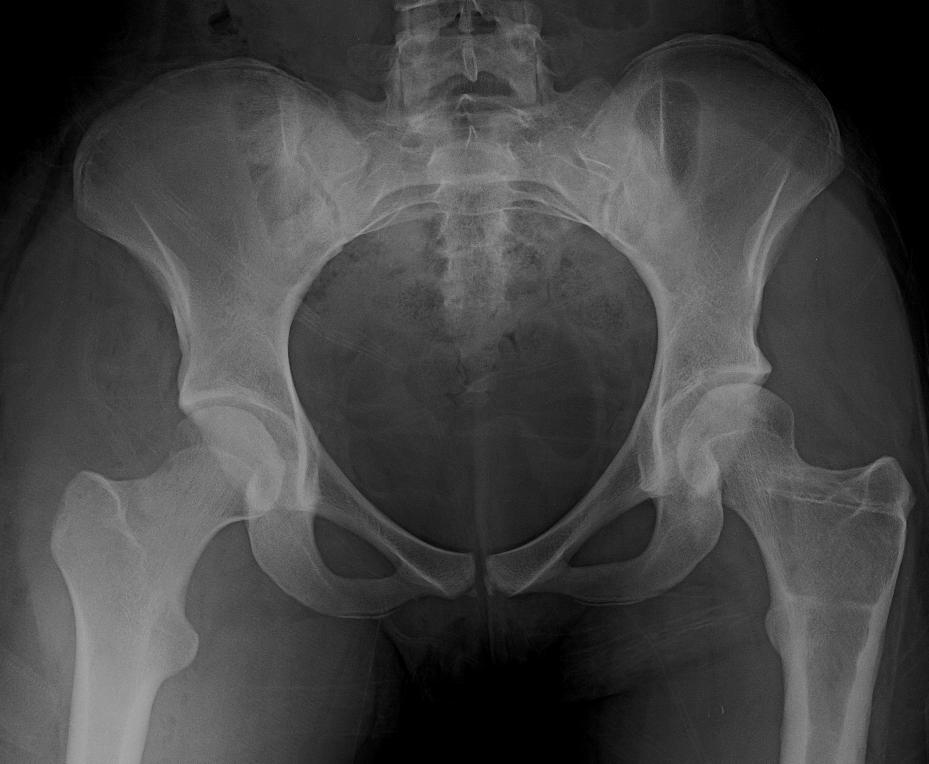

Pelvic radiograph, shows a left hip developmental dysplasia of the hip What Is Considered Mild Hip Dysplasia Severe cases of hip dysplasia are usually diagnosed during a routine screening within the first few. If your healthcare team suspects hip dysplasia,. It measures how well the acetabulum (“hip socket”) covers the head of the femur (“ball” of. Hip dysplasia is most common in babies and young children, but in mild cases, it first shows up in adults. Hip. What Is Considered Mild Hip Dysplasia.